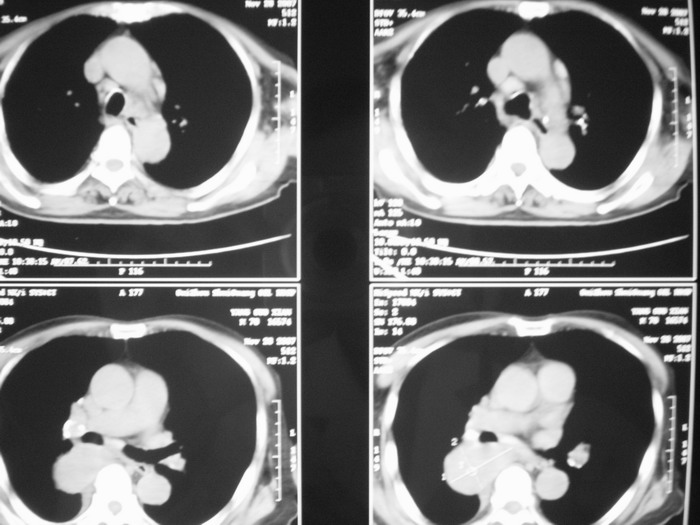

m、70y,反复咳嗽2月。请各位同仁给定位1、(肺?,纵隔?)2、定性。感谢!!

右后纵隔良性占位性病变,神经原性肿瘤可能性大,就其形态看,高密度囊肿待排,建议mri检查。

正位看,支气管分叉角度增大,来源考虑后纵隔的占位,性质考虑1.神经源性肿瘤2.肿大淋巴结

右下肺纵隔旁较大 均匀密度肿块,部分边缘植入纵隔,气管明显受压 变形。支持:后纵隔肿瘤!首选:神经源性!不支持肺内肿瘤原因:1 肿瘤位于下叶支气管及背段支气管开口区,但未侵犯支气管,只是受压表现。2 纵隔内未见肿大淋巴结。3 肺内未见阻塞性肺炎。